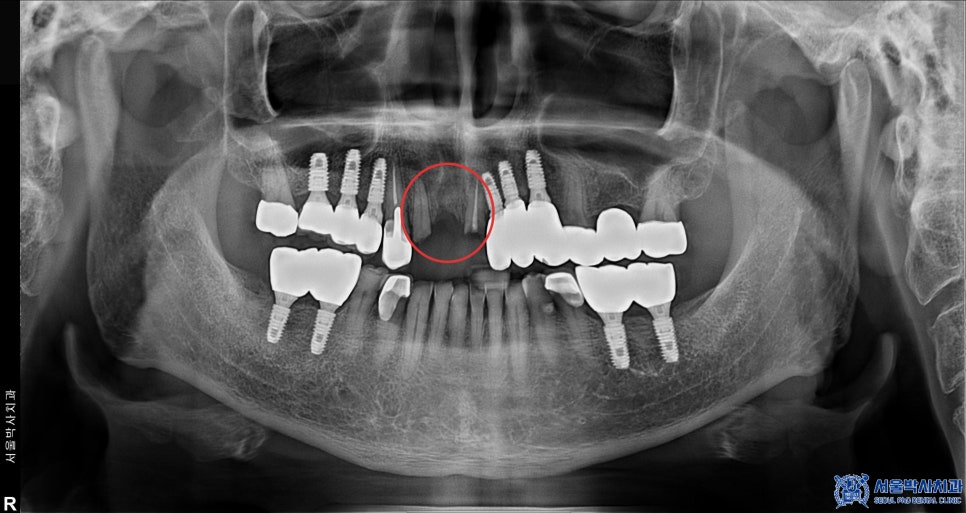

우선, 심한 치주염이 진행된 앞니 두 개를

발치한 뒤 바로 임플란트를

식립하는 방식으로

치료 계획을 세웠습니다.

다만, 환자분의 경우

치조골이 많이 부족한 상태여서

임플란트 식립과 동시에 뼈 이식도

함께 진행하기로 했습니다.